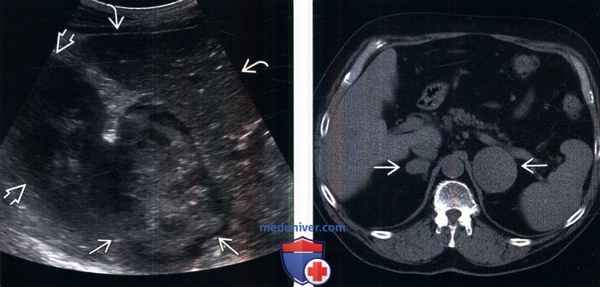

б) Визуализация:

1. Общие характеристики:

• Лучший диагностический критерий:

о Изолированное образование надпочечника с развитием надпочечниковой недостаточности

• Локализация:

о Как правило, вовлечены оба надпочечника, однако описаны и случаи одностороннего поражения

• Размер:

о Крупное мягкотканное образование, часто более 6 см

2. КТ при лимфоме надпочечника:

• Умеренное контрастирование гомогенного солидного образования надпочечника

• Изолированное поражение надпочечника или очевидное преобладание поражения надпочечника при вовлечении внутренних органов/лимфатических узлов:

о Необходимо отличать от вторичного вовлечения надпочечников при распространенной диффузной внеузловой лимфоме

3. МРТ при лимфоме надпочечника:

• Изо/гипоинтенсивное в Т1-ВИ, гиперинтенсивное в Т2-ВИ образование надпочечника

• Равномерное умеренное контрастирование (аналогично КТ с контрастированием)

4. УЗИ при лимфоме надпочечника:

• Двустороннее гипоэхогенное образование надпочечника

5. Радионуклидная диагностика:

• Гиперметаболическое образование при на ФДГ ПЭТ /КТ

6. Рекомендации по визуализации:

• Лучший метод визуализации:

о Специальная КТ надпочечников: опухоль локализуется в надпочечниках, исключение вовлечения других внутренних органов и лимфатических узлов

(Слева) МРТ, Т2-ВИ, TSE, аксиальная проекция: у мужчины 36 лет с общей слабостью и надпочечниковой недостаточностью выявлено двустороннее объемное Т2-интенсивное образование надпочечников.

(Справа) МРТ, усиление гадолинием, постконтрастное Т1-ВИ, коронарная проекция: у этого же пациента выявлены оба образования надпочечников с умеренным контрастированием. Обратите внимание на прямое прорастание опухоли в верхний полюс левой почки. Дифференциальная диагностика включает метастазы в надпочечнике,: однако надпочечниковая недостаточность и отсутствие данных за первичное внепочечное поражение предполагают альтернативный диагноз.

P.S. Последовательность TSE (Turbo-Spin-Echo) - турбо спин-эхо.

(Слева) На УЗИ, выполненным перед биопсией, у этого же пациента выявлено большое образование смешанной эхогенности. расположенное рядом с почкой и печенью. При биопсии установлена В-клеточная лимфома. После терапии по схеме CHOP (циклофосфан, доксорубицин, винкристин, преднизолон) и ритуксимабом была достигнута полная ремиссия.

(Справа) На бесконтрастной КТ, выполненной пожилому мужчине с повышенной утомляемостью и надпочечниковой недостаточностью, выявлено большое образование надпочечника. Дополнительных поражений лимфоузлов или внутренних органов не обнаружено. Диагноз крупноклеточной В-клеточной лимфомы подтвержден после биопсии под контролем УЗИ.